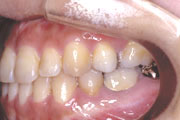

一般矯正の症例

症例2:乱杭歯(叢生)